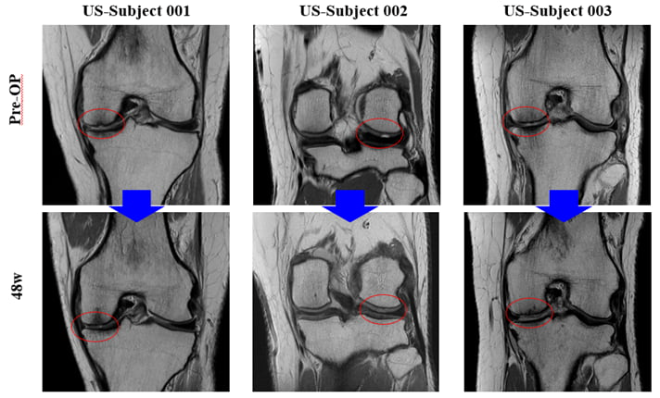

바이오솔루션이 10일(현지 시간) 미국 샌디에이고에서 열린 ‘미국 정형외과 학회(AAOS 2025)’에 참석해 미국 임상 2상 중간결과를 발표했다. 수술 전 환자(위)의 무릎 연골이 수술 후(아래) 개선됐음을 확인할 수 있다. /사진=바이오솔루션 제공

미국 임상 2상은 일부 환자의 MRI 사진을 공개했다. MRI 사진상 연골 결손 부위의 연골 재생 효과가 시술 후 48주까지 일어나는 것이 시각적으로 확연히 나타났다. 또한 가장 중요한 미국 임상 2상의 주 평가지표인 통증 및 운동성 개선 설문(KOOS)뿐만 아니라 VAS, IKDC점수 등에서도 24주, 48주까지 개선 경향이 꾸준히 나타나고 있음을 입증했다.